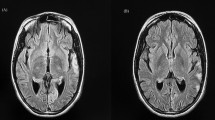

The outcome of severe intractable stroke-like episodes can be fatal. The long-term consequence of recurrent stroke-like episodes is cognitive impairment due to neurodegeneration (Fig. 13.3).

Case Vignette 2

A 17-year-old woman presented to the emergency department with a 2-day history of a constant flashing light in her left hemi-visual field (also with eyes closed), blurred vision and worsening ataxia. She described experiencing intermittent blurred vision, a rainbow of coloured flashes with eyelid flickering lasting around 1 min and headache (described as her worst headache ever) for 2 weeks before attending the emergency department.

She had been diagnosed with recessive POLG-related mitochondrial disease characterized by ataxia, motor-sensory neuropathy and stable epilepsy at the age of 16 years. Her epilepsy was initially managed with topiramate which then changed to carbamazepine due to inefficacy, and levetiracetam was a subsequent add-on therapy. Gabapentin was started for neuropathic pain.

On admission, her GCS was 15 and left homonymous hemianopia was evident. Other positive neurological findings were mild, distal ankle weakness, areflexia and sensory loss below the knee level. Stroke-like episode and prolonged occipital seizures were suspected; carbamazepine and levetiracetam were increased to 400 mg BD and 1750 mg, respectively, and clobazam 10 mg BD was added. MRI head performed a week after the onset of positive visual phenomena identified T2-signal abnormalities involving the right medial occipital lobe with cytotoxic changes (Fig. 13.4a–d). Her EEG demonstrated an active ictal focus over the right posterior quadrant with occasional epileptic discharges within the contra-lateral parieto-occipital region. A decision for escalating to general anaesthesia treatment was made given the patient had developed refractory non-convulsive status epilepticus (occipital seizures) and unilateral visual field loss. Burst suppression pattern was achieved and maintained with the combined administration of midazolam (265 mg) and thiopentone (18,875 mg) over 3 days. She remained in a comatose state for 6 days after stopping thiopentone. Repeat MRI head (day 7) showed resolution of signal abnormalities in the right occipital lobe and corpus callosum (Fig. 13.4e–h). Her ICU stay was complicated by hospital-acquired pneumonia and clostridium difficile diarrhoea, which were treated with appropriate antibiotics. Extubation was successfully performed 10 days after ICU admission, and the patient was stepped down for rehabilitation on day 14. However, a left-sided visual field loss returned 5 days later, but without positive visual phenomena on this occasion. Her EEG only showed encephalopathic changes; repeat MRI head (day 22) showed a stroke-like lesion that had appeared in the same location as per the previous scan but without restricted diffusion (Fig. 13.4i–l).